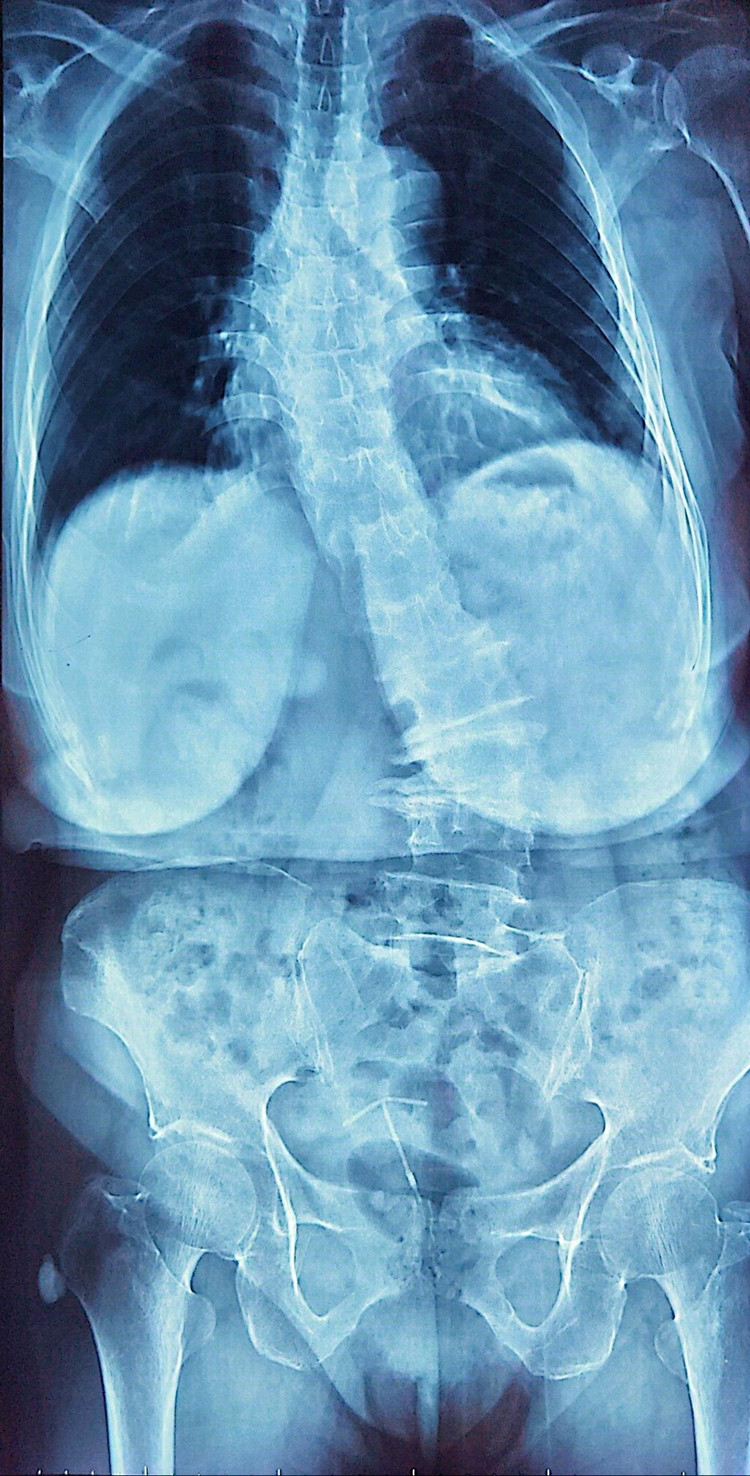

| Hình ảnh loãng xương trên phim chụp - Ảnh BSCC |